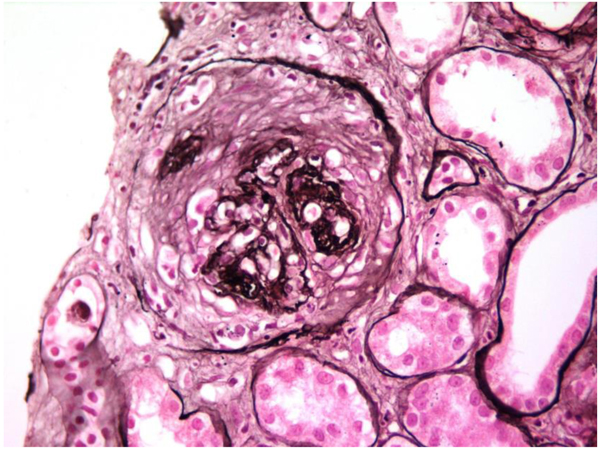

Allograft biopsy showed 7 viable glomeruli with active circumferential crescents in 5 (Fig. 1). There was a mild degree of tubulointerstitial chronicity. Immunofluorescence staining showed strong linear IgG along the glomerular capillary base ment membranes and occasionally along distal tubular basement membranes (Fig. 2). A diagnosis of Anti-glomerular basement membrane nephritis with crescentic transformation was made.

In view of the positive anti-GBM antibody, plasmapheresis was continued. In all, 23 sessions were given. However, the graft function did not improve and deteriorated relentlessly over the next six months. A repeat graft biopsy was performed 6 months later to the first biopsy and revealed fibrous crescents in all 8 glomeruli (Fig. 3) with moderate tubule-interstitial chronicity. Immunofluorescence continued to reveal similar findings as first biopsy (Fig. (4). She is currently on continuous ambulatory peritoneal dialysis, waiting to receive a deceased donor kidney.